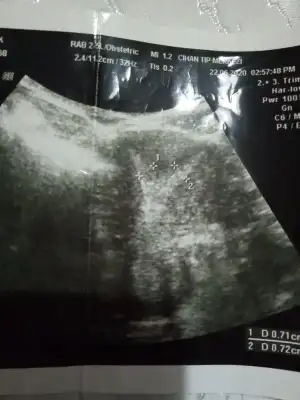

Velhasılı kelam ben de 2 kere düşük yaptım, bu rahim şekliyle gebe kalabilmek oldukça zor iken gebe kalabiliyoruz bu harika. Fakat perdeden dolayı 2 gebeliğimde de 15. Hafta hep düşük yaptım. Histeroskopi oldum, perde alındı. Şuan artık gebeliğimde düşük olmaması gerekiyormuş. Gebe kalabilmeyi bekliyorum.

Sana rahmimin ameliyat öncesi ve sonrasını gönderiyorum fikrin olması açısından